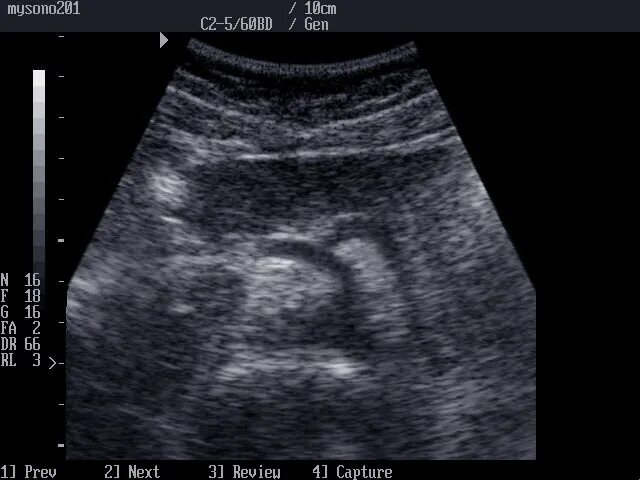

Узи кишечника как подготовиться